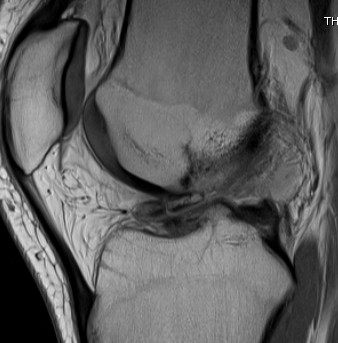

MRI

2 x Osteochondral Fragments in Notch

Osteochondral Fragment in PFJ

Loose body in posterolateral compartment